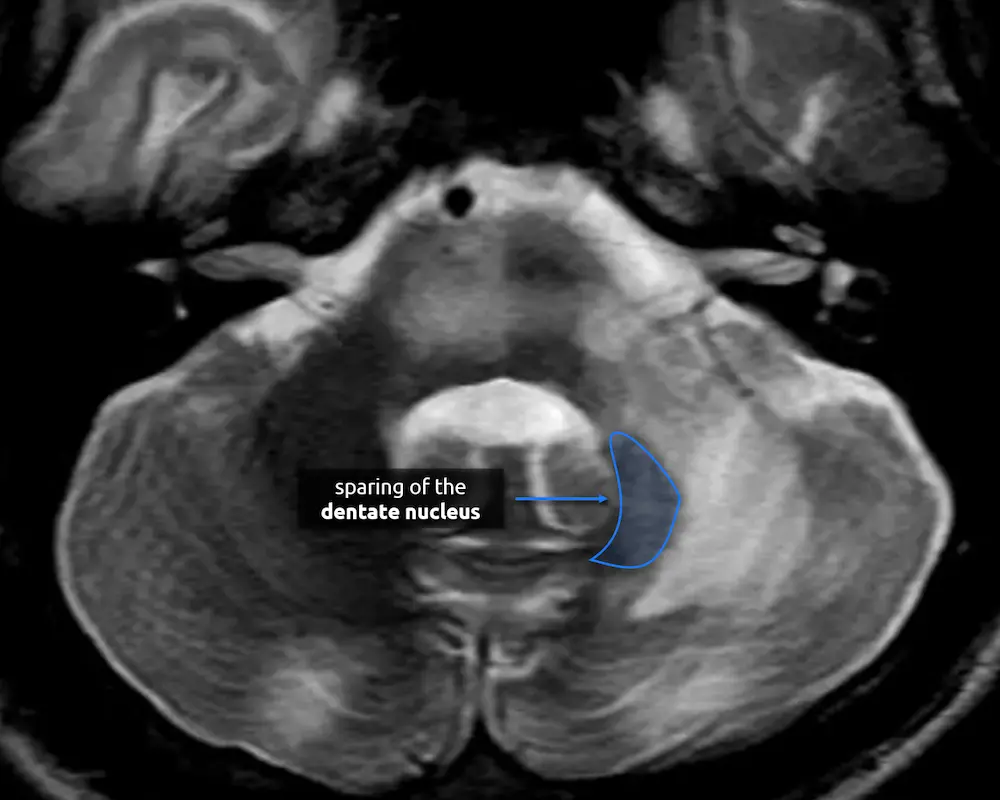

There are four deep cerebellar nuclei that are responsible for all of the signals leaving the cerebellum. The largest, most lateral, and only one that is easily identifiable on routine brain imaging is the dentate nucleus.

A 45-year-old woman with HIV presents with ataxia and altered mental status.

a. What part of the cerebellum is more affected by the signal abnormality: the white matter or the gray matter?